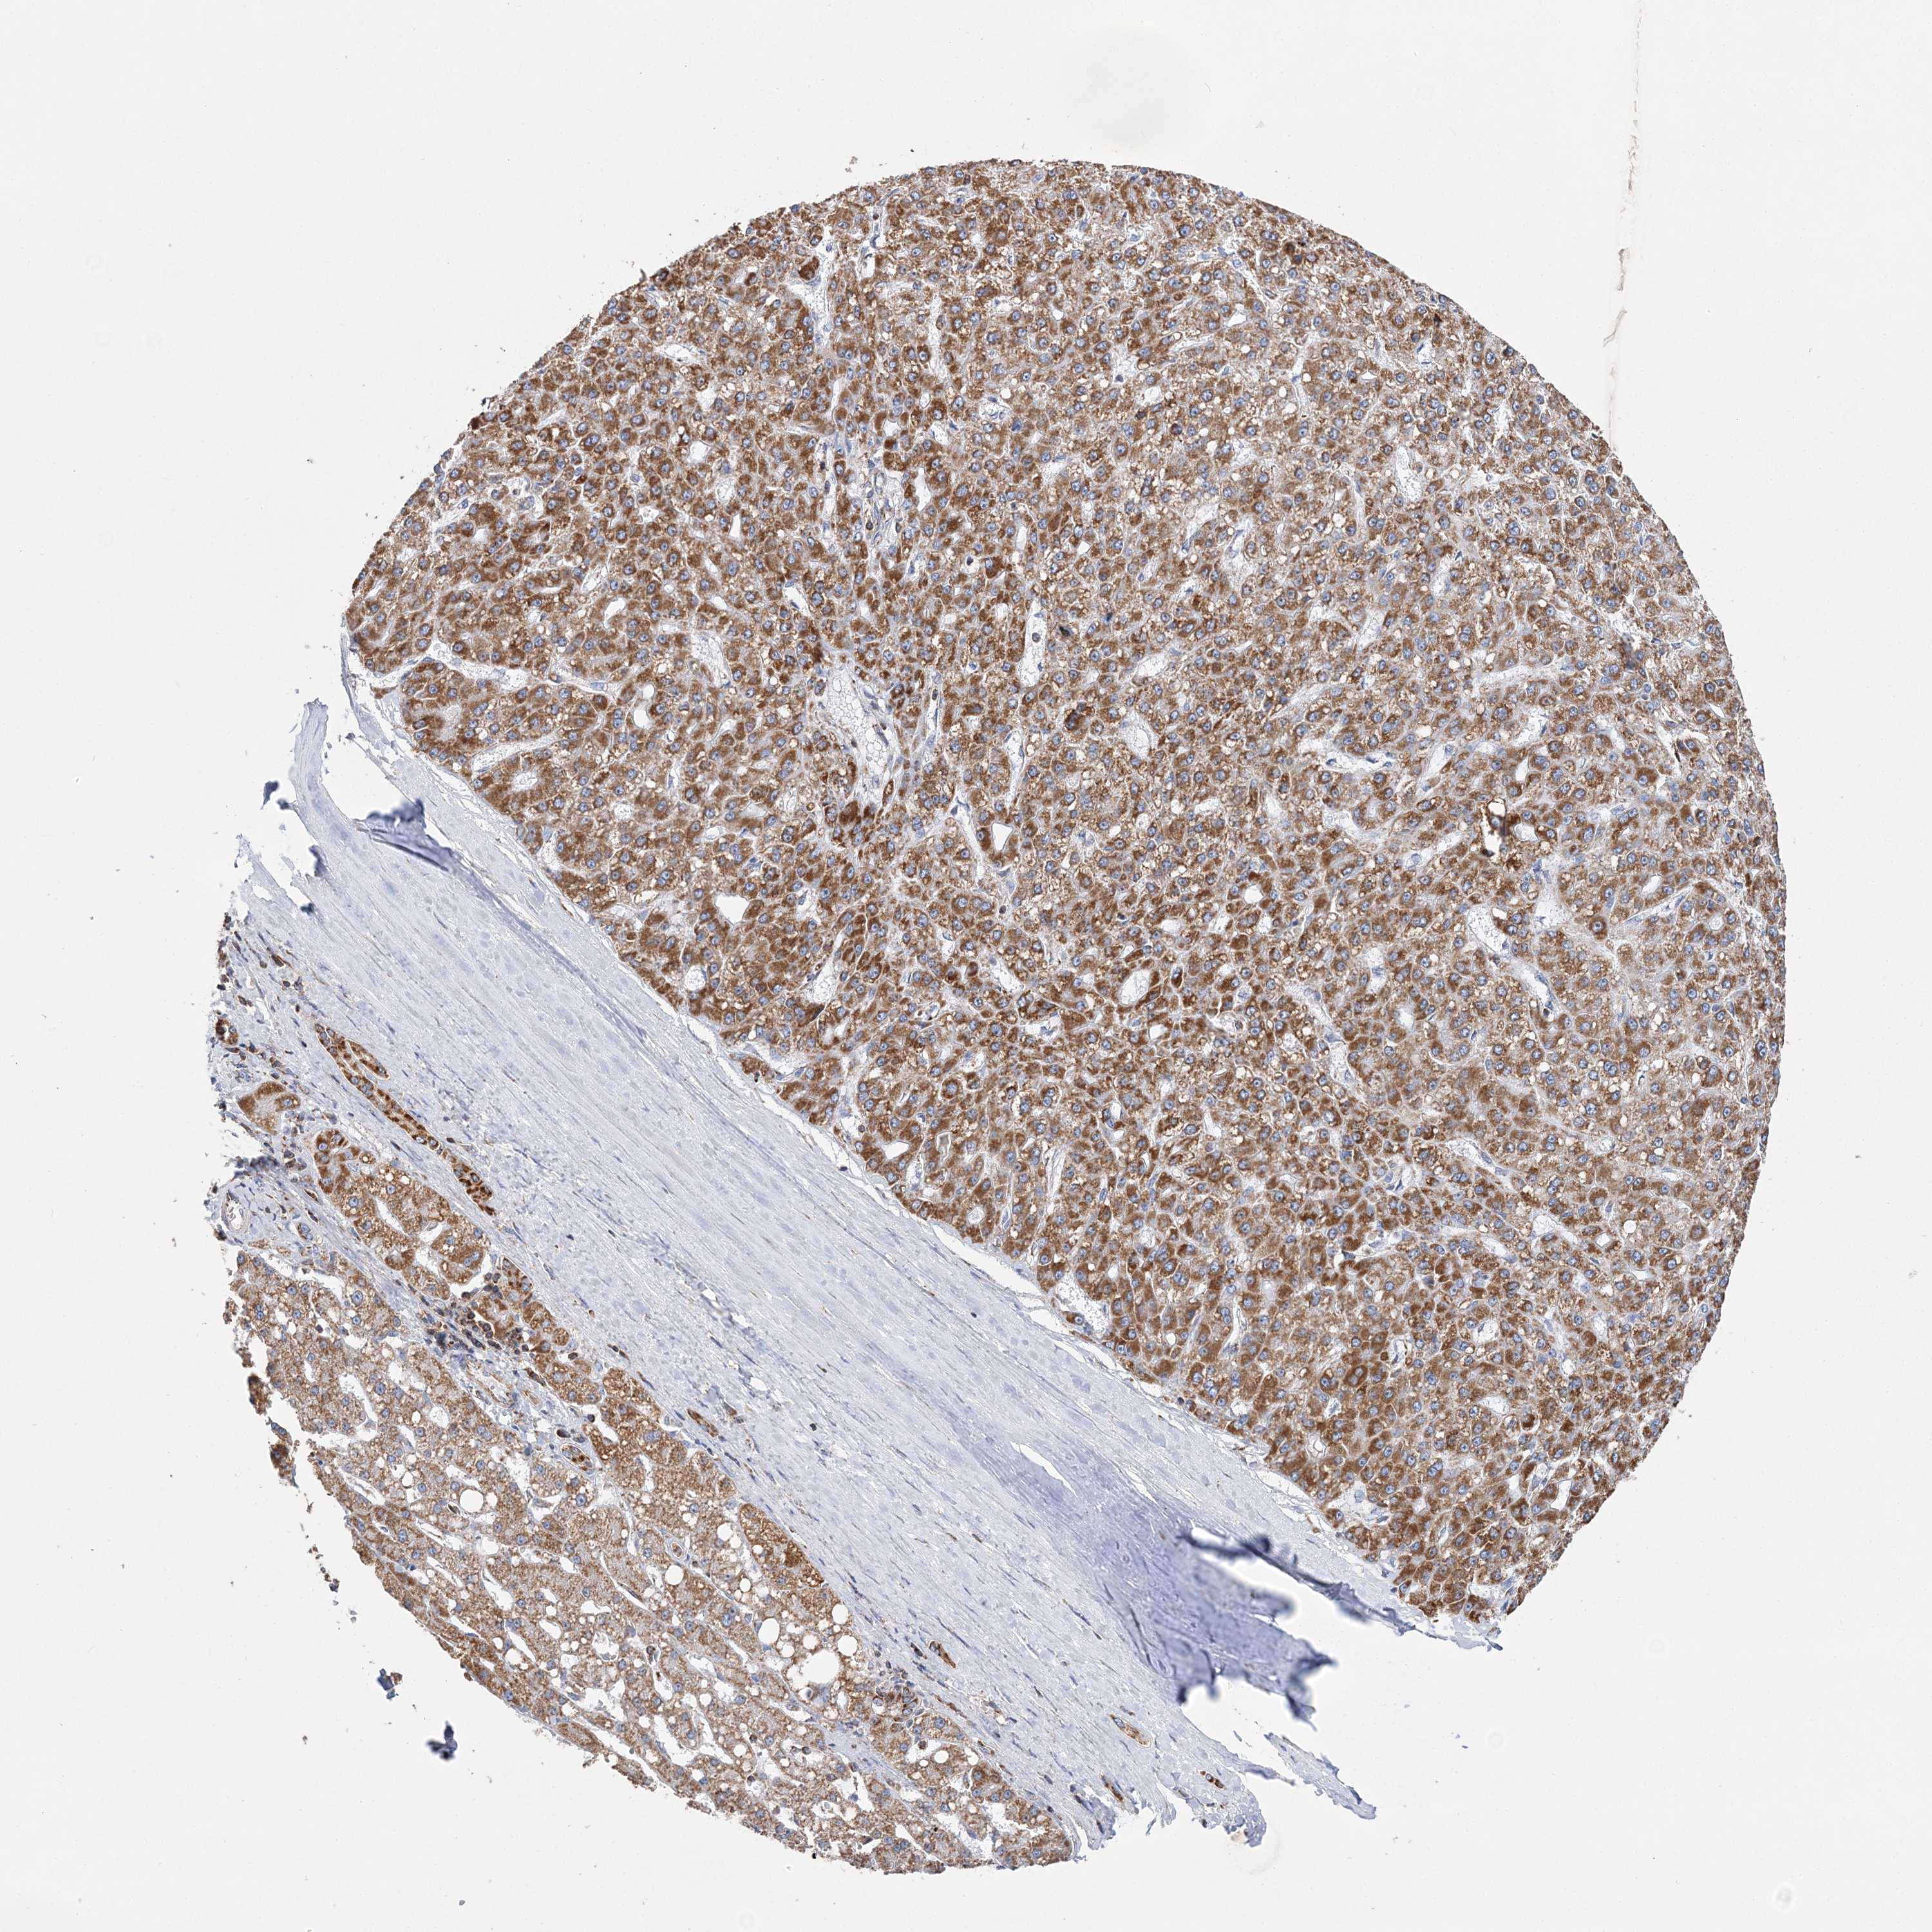

LIVER CANCER - Protein expressioni

A mouse-over function shows sample information and annotation data. Click on an image to view it in a full screen mode. Samples can be filtered based on level of antibody staining by selecting one or several of the following categories: high, medium, low and not detected. The assay and annotation is described here.

Note that samples used for immunohistochemistry by the Human Protein Atlas do not correspond to samples in the TCGA dataset.

Antibody stainingi

Antibody staining in the annotated cell types in the current human tissue is reported as not detected, low, medium, or high, based on conventional immunohistochemistry profiling in selected tissues. This score is based on the combination of the staining intensity and fraction of stained cells.

Each image is clickable and will lead to virtual microscopy that enables deeper exploration of all samples and also displays staining intensity scores, fraction scores and subcellular localization as well as patient and tissue information for each sample.

Antibody HPA036024

Staining

High

Medium

Low

Not detected

Intensity

Strong

Moderate

Weak

Negative

Quantity

>75%

75%-25%

<25%

None

Location

Nuclear

Cytoplasmic/membranous

Cytoplasmic/membranous,nuclear

Cholangiocarcinoma

Carcinoma, Hepatocellular, NOS